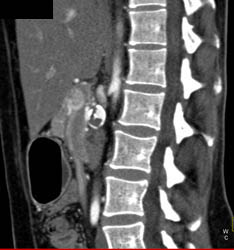

Hepatic Artery Aneurysm